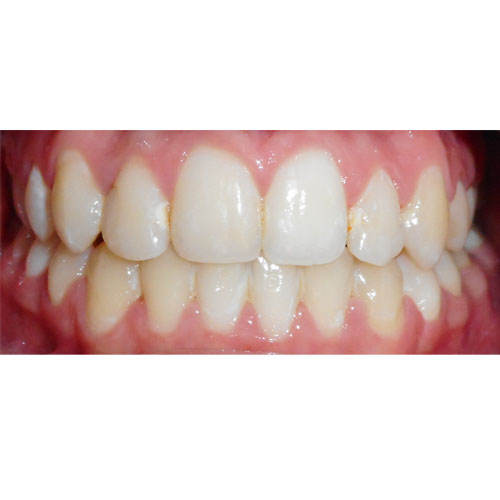

Nasze rezultaty